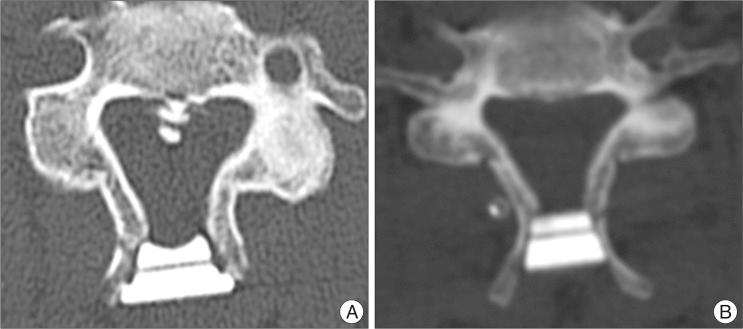

During January 2004 and January 2010, 45 patients with compressive cervical myelopathy underwent midline-splitting open door laminoplasty with winged (33 cases) and wingless (12 cases) HAs by a single surgeon. Minimal and mean follow up times were 12 and 28.1 months, respectively. Japanese Orthopedic Association (JOA) score was used for clinical outcome measurement. Cervical X-rays were taken preoperatively, immediately post-operatively, and after 3, 6, and 12 months and computed tomography scans were performed preoperatively, immediately post-operatively and after 12 months. Cervical lordosis, canal dimension, fusion between lamina and HA, and affecting factors of fusion were analyzed.

All surgeries were performed on 142 levels, 99 in the winged and 43 in the wingless HA groups. JOA scores of the winged group changed from 10.4±2.94 to 13.3±2.35 and scores of the wingless group changed from 10.8±2.87 to 13.8±3.05. There was no significant difference on lordotic and canal dimensional change between two groups. Post-operative 12 month fusion rate between lamina and HA was significantly lower in the winged group (18.2 vs. 48.8% p=0.001). Multivariate analysis showed that ossification of the posterior longitudinal ligament, male gender, and wingless type HA were significantly associated with fusion.

Clinical outcome was similar in patients receiving winged and wingless HA, but the wingless type was associated with a higher rate of fusion between HA and lamina at 12 months post-operatively.

方法

2004年1月至2010年1月期间,45例压迫性颈椎病患者由同一位外科医生采用带翼(33例)和无翼(12例)HA行中线劈开开门式椎板成形术。最短和平均随访时间分别为12个月和28.1个月。采用日本骨科协会(JOA)评分评估临床疗效。术前、术后即刻、术后3、6和12个月拍摄颈椎X线片,术前、术后即刻和术后12个月进行计算机断层扫描。分析颈椎前凸、椎管尺寸、椎板与HA之间的融合情况以及融合的影响因素。

结果

所有手术共涉及142个节段,带翼HA组99个节段,无翼HA组43个节段。带翼组JOA评分从10.4±2.94变为13.3±2.35,无翼组评分从10.8±2.87变为13.8±3.05。两组之间在颈椎前凸和椎管尺寸变化方面无显著差异。术后12个月时,带翼组椎板与HA之间的融合率显著低于无翼组(18.2%对48.8%,p = 0.001)。多因素分析显示,后纵韧带骨化、男性性别和无翼型HA与融合显著相关。

结论

接受带翼和无翼HA的患者临床疗效相似,但无翼型在术后12个月时HA与椎板之间的融合率更高。